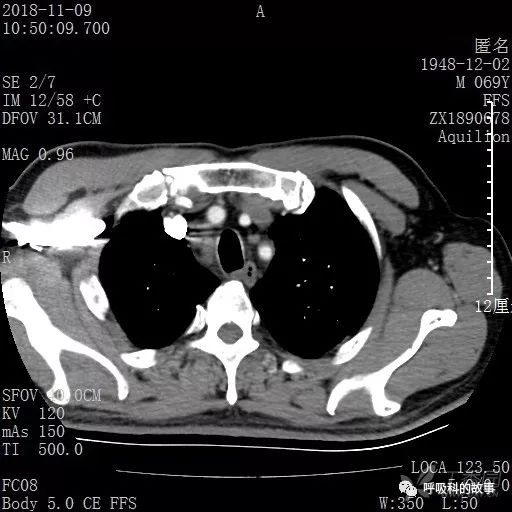

胸部增强CT示右肺门占位伴远端阻塞性肺炎,纵膈、右肺门、右侧颈根部、右侧腋下及肝门部肿大淋巴结。两侧胸腔少量积液。

纵隔窗的增强CT

肺窗CT